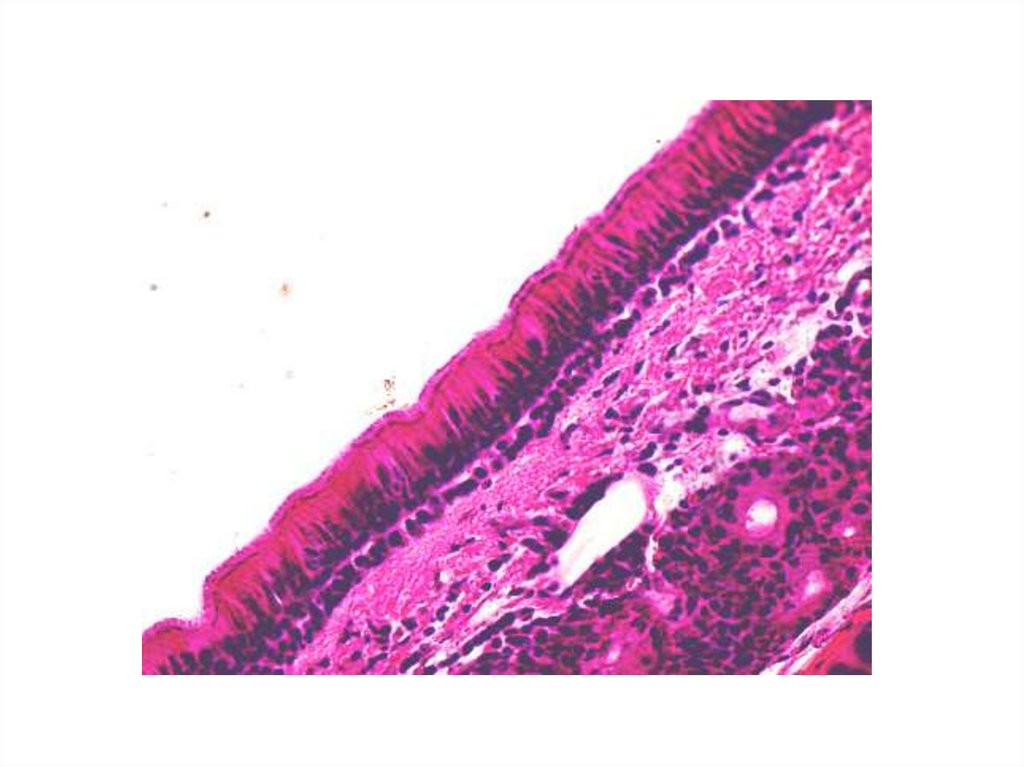

4 - эпителий трахеи

5 - эпителий кожи пальца